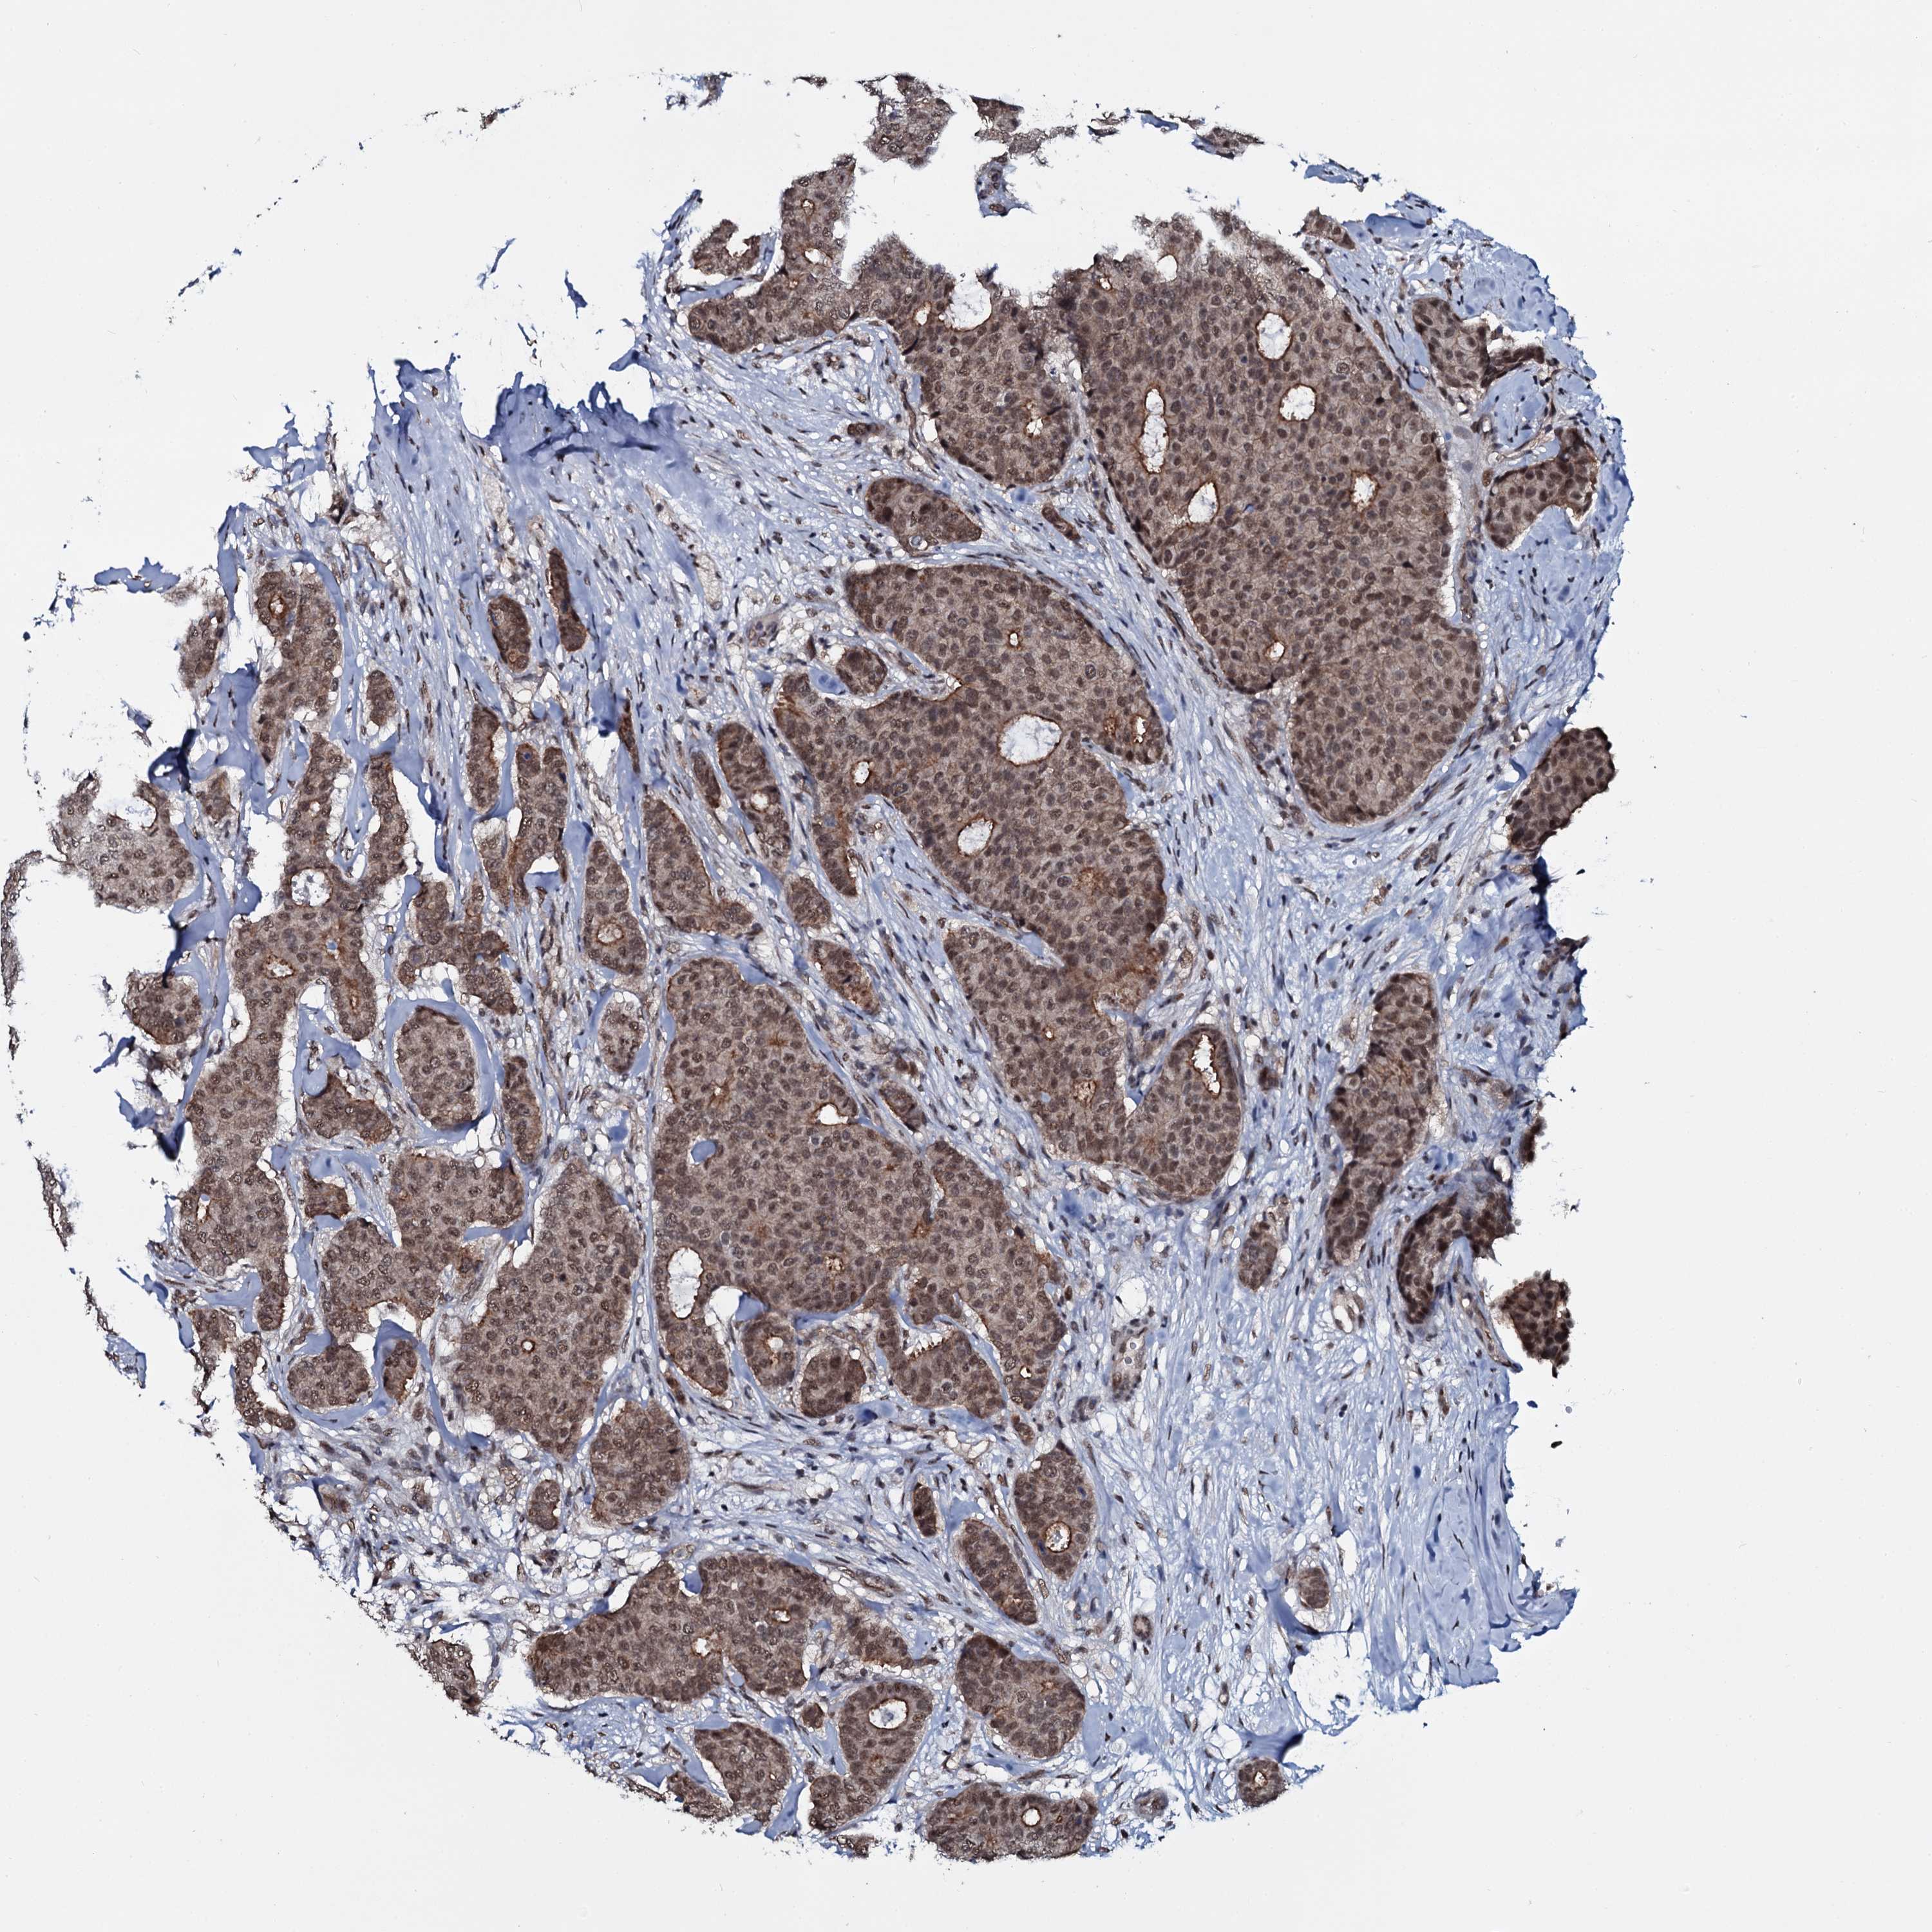

CANCER BREAST CANCER Show tissue menu

BRCA TCGA BRCA VALIDATION PROTEIN EXPRESSION